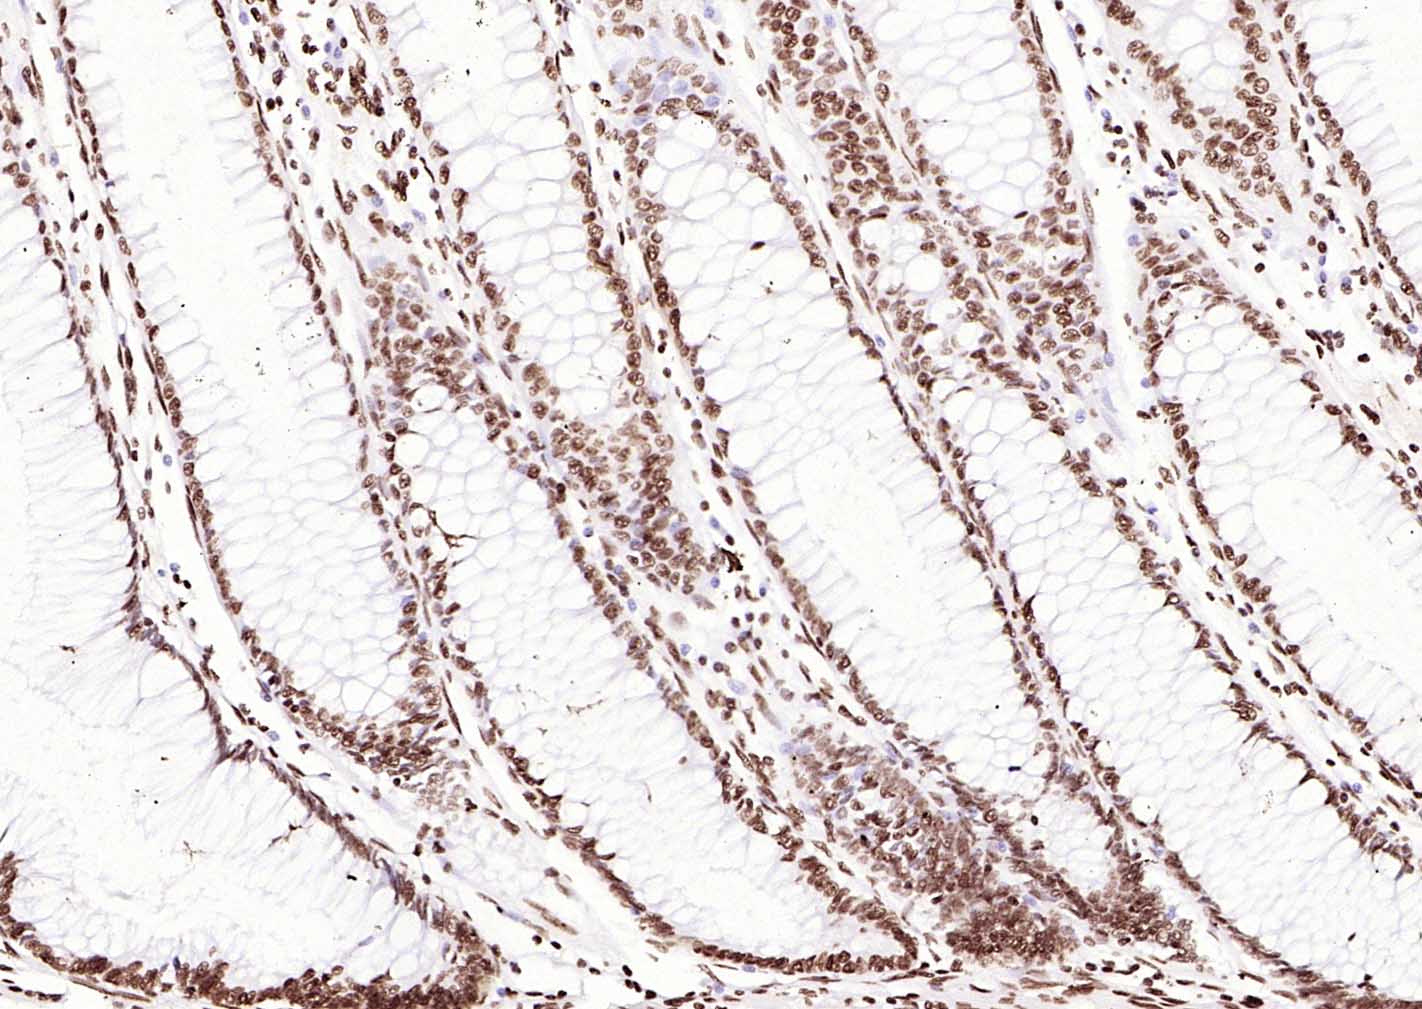

Paraformaldehyde-fixed, paraffin embedded (human pancreatic cancer); Antigen retrieval by boiling in sodium citrate buffer (pH6.0) for 15min; Block endogenous peroxidase by 3% hydrogen peroxide for 20 minutes; Blocking buffer (normal goat serum) at 37°C for 30min; Incubation with (ERCC1 ) Monoclonal Antibody, Unconjugated (bsm-60230R) at 1:500 overnight at 4°C, followed by operating according to SP Kit(Rabbit) (sp-0023)instructionsand DAB staining.